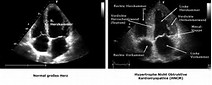

Die Echokardiografie, so nennt man die Untersuchung des Herzens mittels Ultraschall, ist die Echokardiografie eine der wichtigsten technischen nichtinvasiven Untersuchungsmethoden des Herzens und mittlerweile unverzichtbarer Bestandteil der kardiologischen Diagnostik.

Mit Hilfe der Herzsonographie erhält der Arzt Aufschluss über die Struktur von Herzwänden und Herzklappen und deren Bewegungsabläufe, über Wanddicke von Herzvorhöfen und Herzkammern, die Größe der Herzbinnenräume und damit die gesamte Herzgröße, sowie die Auswurfleistung des Herzens.

Anhand dieser Informationen können folgende Erkrankungen diagnostiziert oder in ihrem Verlauf dokumentiert werden (Verlaufskontrolle):Herzklappen-Erkrankungen, Herzmuskel-Erkrankungen (Kardiomyopathien), Fehlbildungen der Hauptschlagader (Aorta) oder der Herzwand.